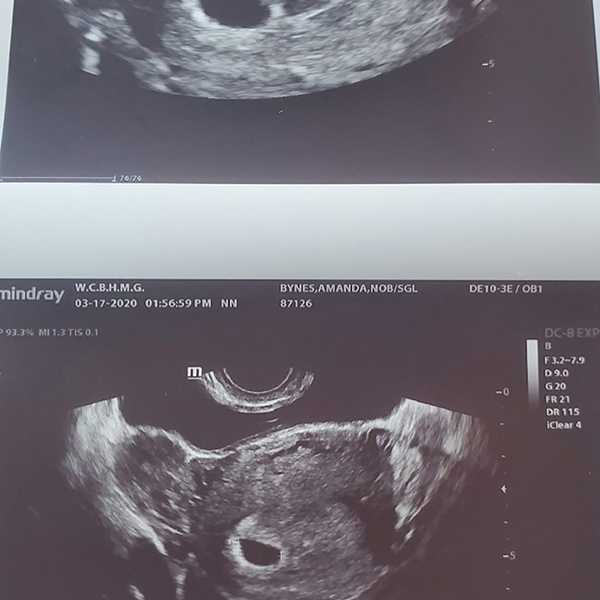

Su abogado David Esquibias dice que la actriz no está embarazada. Amanda anunció en su Instagram que tenía un baby on board, el 17 de marzo. Su prometido, publicó los mismo en sus redes, con una foto de la pareja. También publicó el ultrasonido que tenía el nombre de Bynes. O sea! LOOK AT ME!!!